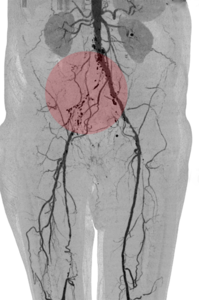

Therapeutische Verfahren - Interventionen

Zur Behandlung von Gefäßerkrankungen stehen uns neben Gefäßoperationen auch minimal invasive Therapiemethoden zur Verfügung. Hierzu gehören Eingriffe an Arterien oder Venen der Arme und Beine, des Halses sowie des Brust- und Bauchraumes. Diese werden über einen durch Punktion geschaffenen Gefäßzugang mit Hilfe spezieller Drähte, Katheter u. ä. durchgeführt. In der Regel sind diese Interventionen sehr schmerzarm.

Nachfolgend erhalten Sie einen Überblick der gängigen Methoden, die im Oberlausitzer Gefäßzentrum zur Anwendung kommen. Abhängig vom Schweregrad der Durchblutungsstörung erfolgt oft eine Kombination der verschiedenen Verfahren.